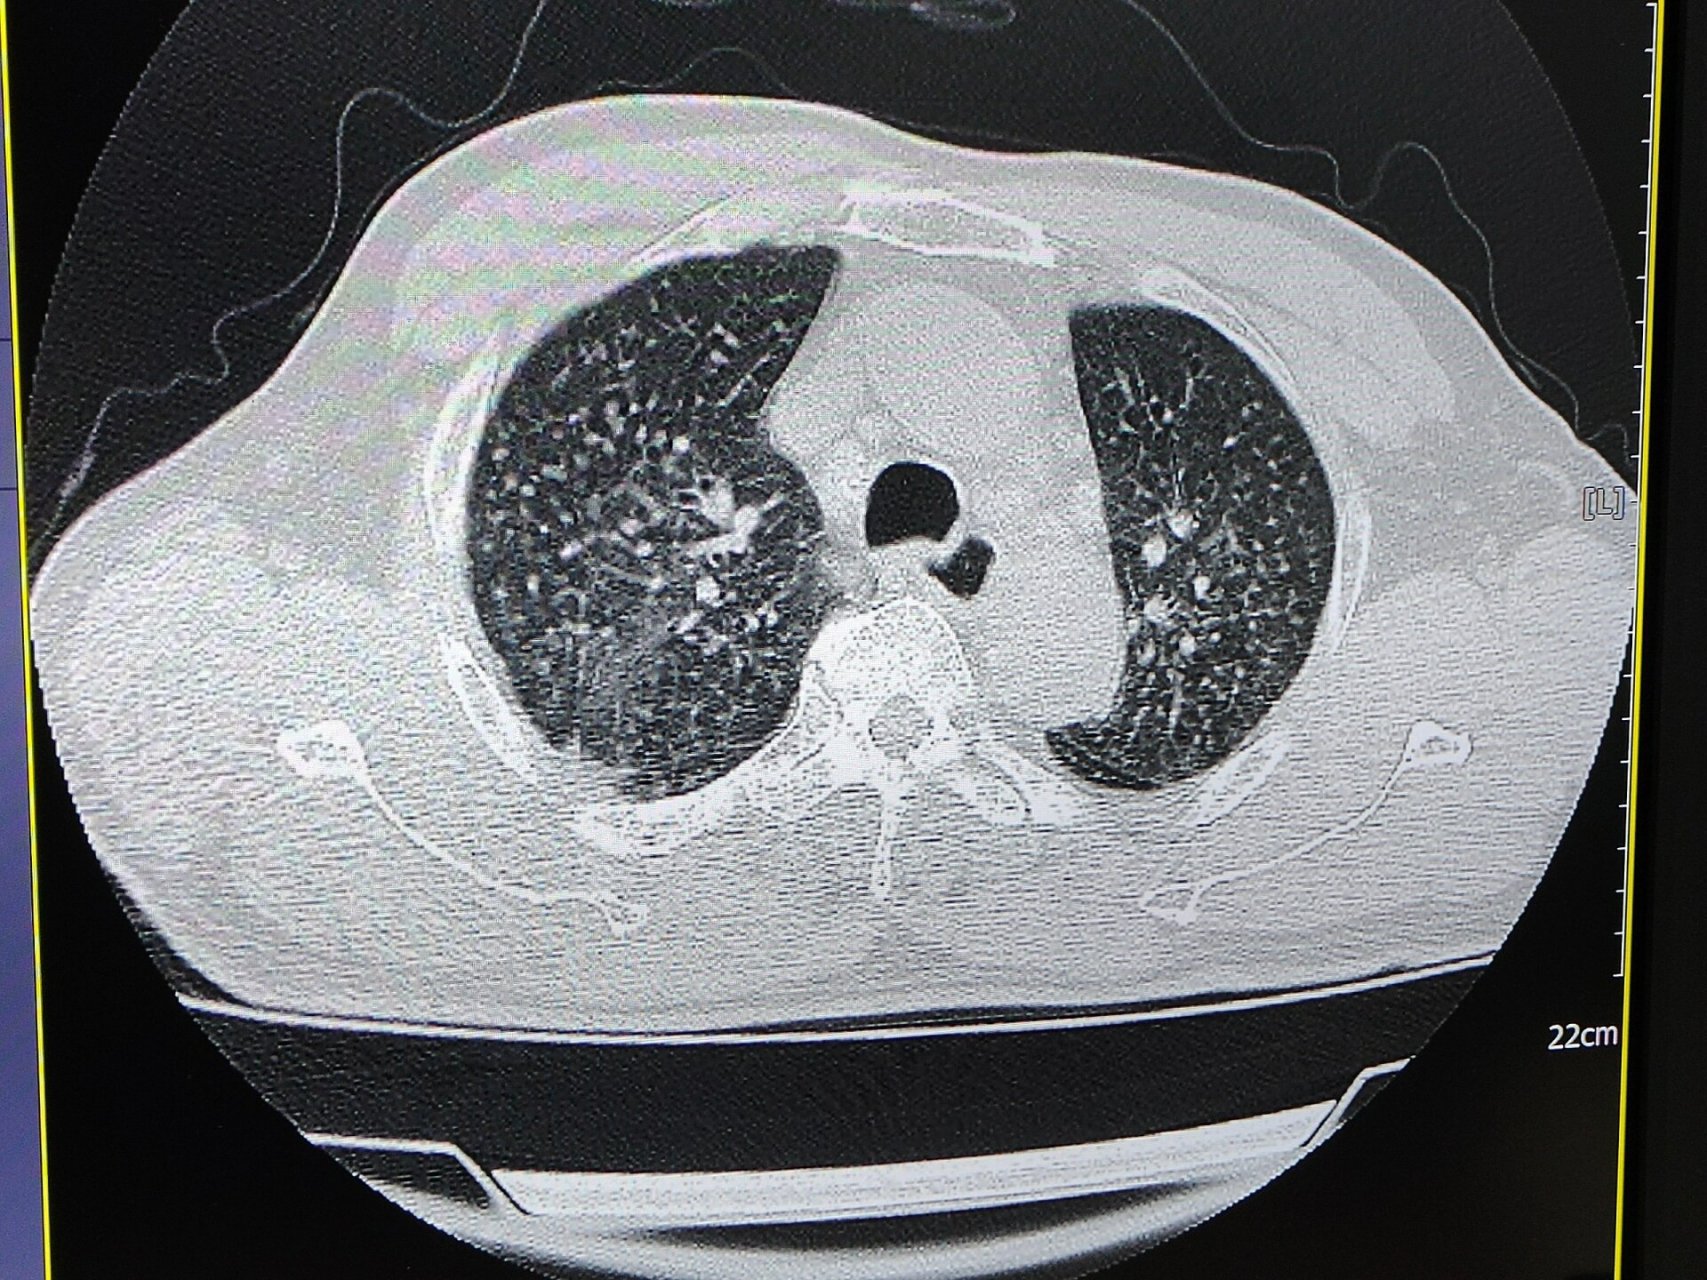

矽肺ct表现 两肺见弥漫多发粟粒结节影,可以看到两肺门,纵隔淋巴结轻

早期矽肺ct特征表现为双肺多发,无融合的小结节影,大小不等,多为2